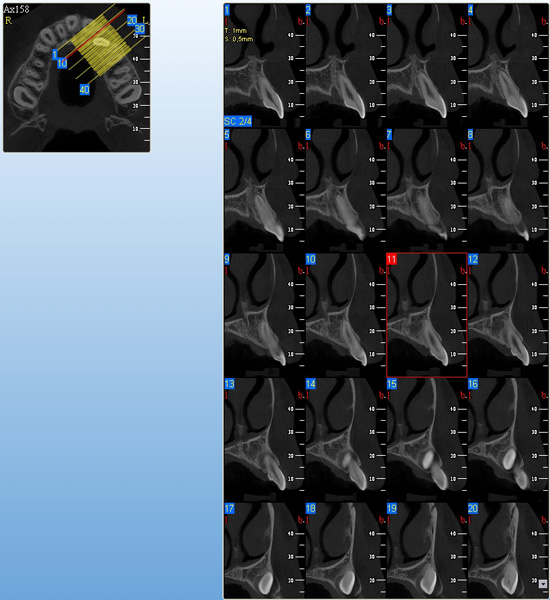

3D DVT - NewTom

Je speciální zubní digitální tříprostorový tomograf (3D), který umožňuje na základě jediného snímkování vytvořit všechny typy RTG zobrazení, které jsou pro lékaře potřebné. Díky používané technologii tzv. „kuželového paprsku“ a speciálním senzorům je výrazně zmenšená dávka záření - o více jak 80% proti klasickému CT vyšetření. To je významné zejména u dětí. Pomocí tohoto přístroje je možné zjisti skutečnou situaci v čelistních kostech pacienta tedy množství kosti - můžeme změřit skutečnou šířku i výšku kosti, i kvalitu kosti (hustotu) v místě uvažované implantace. 3D (tříprostorové) zobrazení umožňuje zvýšit prostorovou představu operatéra ještě před vlastní operací a zároveň pacientovi lépe objasnit a ukázat oblast plánovaného zavedení implantátu.

Pacient „neumí číst“ RTG snímky, ale díky 3D zobrazení vidí „svoji skutečnou čelist“ - např. jak je nízká či úzká, vidí průběh nervu nebo velikost čelistní dutiny, což mu umožní i pochopení nutnosti v některých případech provést pomocné zákroky ještě před vlastním zavedením implantátu (viz. kostní štěp, sinus lift, kostní granulát...).

Vyšetření pomocí tohoto přístroje používáme i ve stomatochirurgii (zlomeniny čelistí, zuby moudrosti, cysty, onemocnění čelistního kloubu), ortodoncii (retinované zuby, nadpočetné zuby), parodontologii atd.